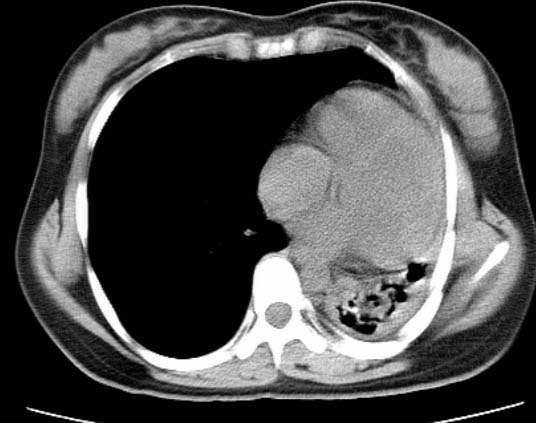

女  20岁。一月前咳血,诊“肺结核”抗痨治疗一月后,咳血停止,现复查。病人精神好。前后ct片对比未见明显变化。既往体检“正常”

1)考虑左肺结核并肺不张、支气管扩张。2)纵隔疝。

以前体检正常只能考虑左肺结核并肺不张、支气管扩张。2)纵隔疝。

考虑左肺结核,左肺毁损,纵膈左偏,既往体检正常不可靠,tb一个月也不会这个样子的,有钙化,应该病程较长,冰冻三尺非一日之寒!

左肺发育不全。

考虑左肺结核,左肺毁损,纵膈左偏,既往体检正常不可靠,tb一个月也不会这个样子的,有钙化,应该病程较长,冰冻三尺非一日之寒

结核,左肺毁损。